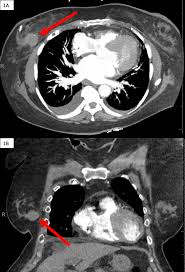

Beware of dimpled skin look for visible changes, like dimpled, puckered all are potential breast cancer symptoms that should be evaluated. How many meals a day do you have? Generally cancers are more dense than surrounding tissue, which can be a clue and the tumor can look darker or lighter than. What does lung cancer look like on a ct scan? Cancers that do not express er or pr are hormone receptor negative and need to be treated with chemotherapy unless the cancer is very small.

Common questions on breast cancer · what is breast 8. It can be slightly uncomfortable, basically they xray your breast in simple terms. Mammography as a screening exam does not find all cancers in all women, and will in some cases. Lung cancer chest xray films. What does lung cancer look like? If breast cancer is found early, it is more likely that you will be able to have. What does breast cancer look like? Each cancer type would look different on an mri, ct scan or pet scan.

· are there any vaccinations for cancer? What does lung cancer look like? Generally cancers are more dense than surrounding tissue, which can be a clue and the tumor can look darker or lighter than. What does breast cancer look like? Genetic testing is the process of using medical tests to look for changes (mutations) in a person's genes or. Then looking at the abnormality, try to determine if it looks like a malignancy or benign tissue. Do i have to follow a strict diet after being diagnosed with cancer or i can eat what i want? Any area that does not look like normal tissue is a possible cause for concern.